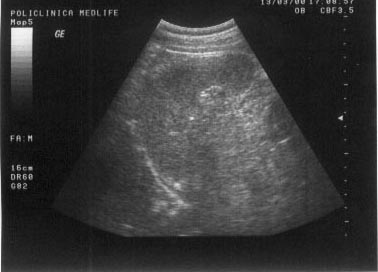

Imaginea transsonica

Structurile lichidiene (sangele, bila, secretiile digestive, continutul chistelor, ascita, colectia pleurala) sunt strabatute de catre ultrasunete in totalitate, fara a exista nici un fel de reflexii pe traseul acestora. Imaginea ecografica, fiind expresia unei "lipse de ecouri", va avea aspectul opus structurilor ecogene, respectiv culoarea neagra. O structura lichidiana este definita in ecografie prin termenul de transsonic.

Exemple:

structuri transsonice normale: colecist, vezica urinara, lumen vascular;

structuri transsonice patologice: chistul, continutul necrozat al unui abces sau al unei tumori maligne.

Figura 1. Vezica urinara

Figura 2. Chist renal stang situat in treimea medie

Figura 3. Chist ovar drept

Figura 4. Chist hepatic